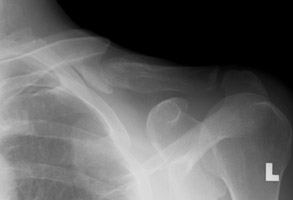

- Click on the image for a larger versionAAP radiograph of the left clavicle. There is an acute mid-clavicular fracture.